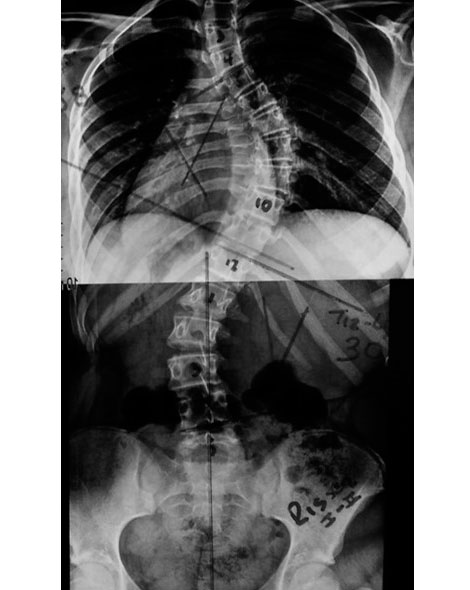

¿CÓMO SE VE LA ESCOLIOSIS EN LA RADIOGRAFÍA?

El mas usado es el signo de risser que nos permite evaluar la aparición del nucleo de osificación en la cresta iliaca